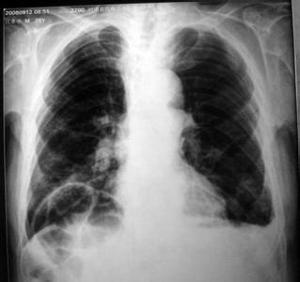

本病的診斷主要是X線與CT,現在也用超音波檢查。